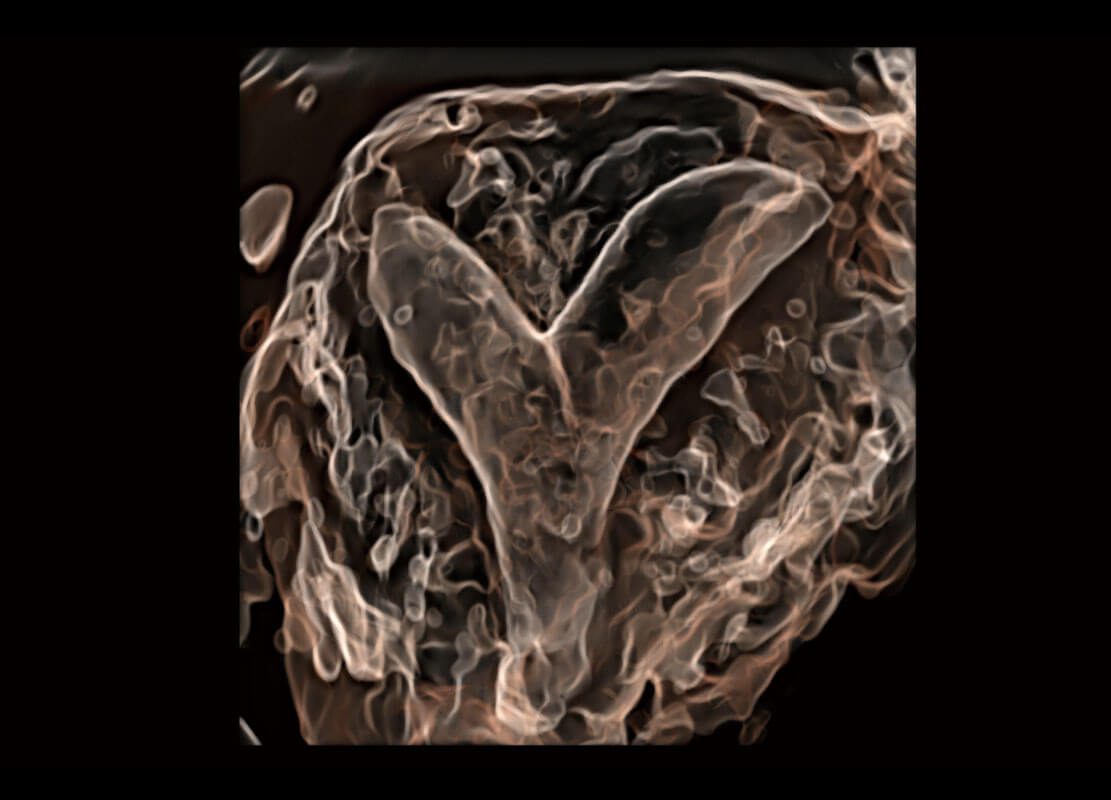

胎心筛查

P60搭载一系列胎儿心脏成像技术,实现精细的胎儿心脏评估。

• 四腔切面

• 四腔心血流

• 右室双出口

• 胎心容积成像